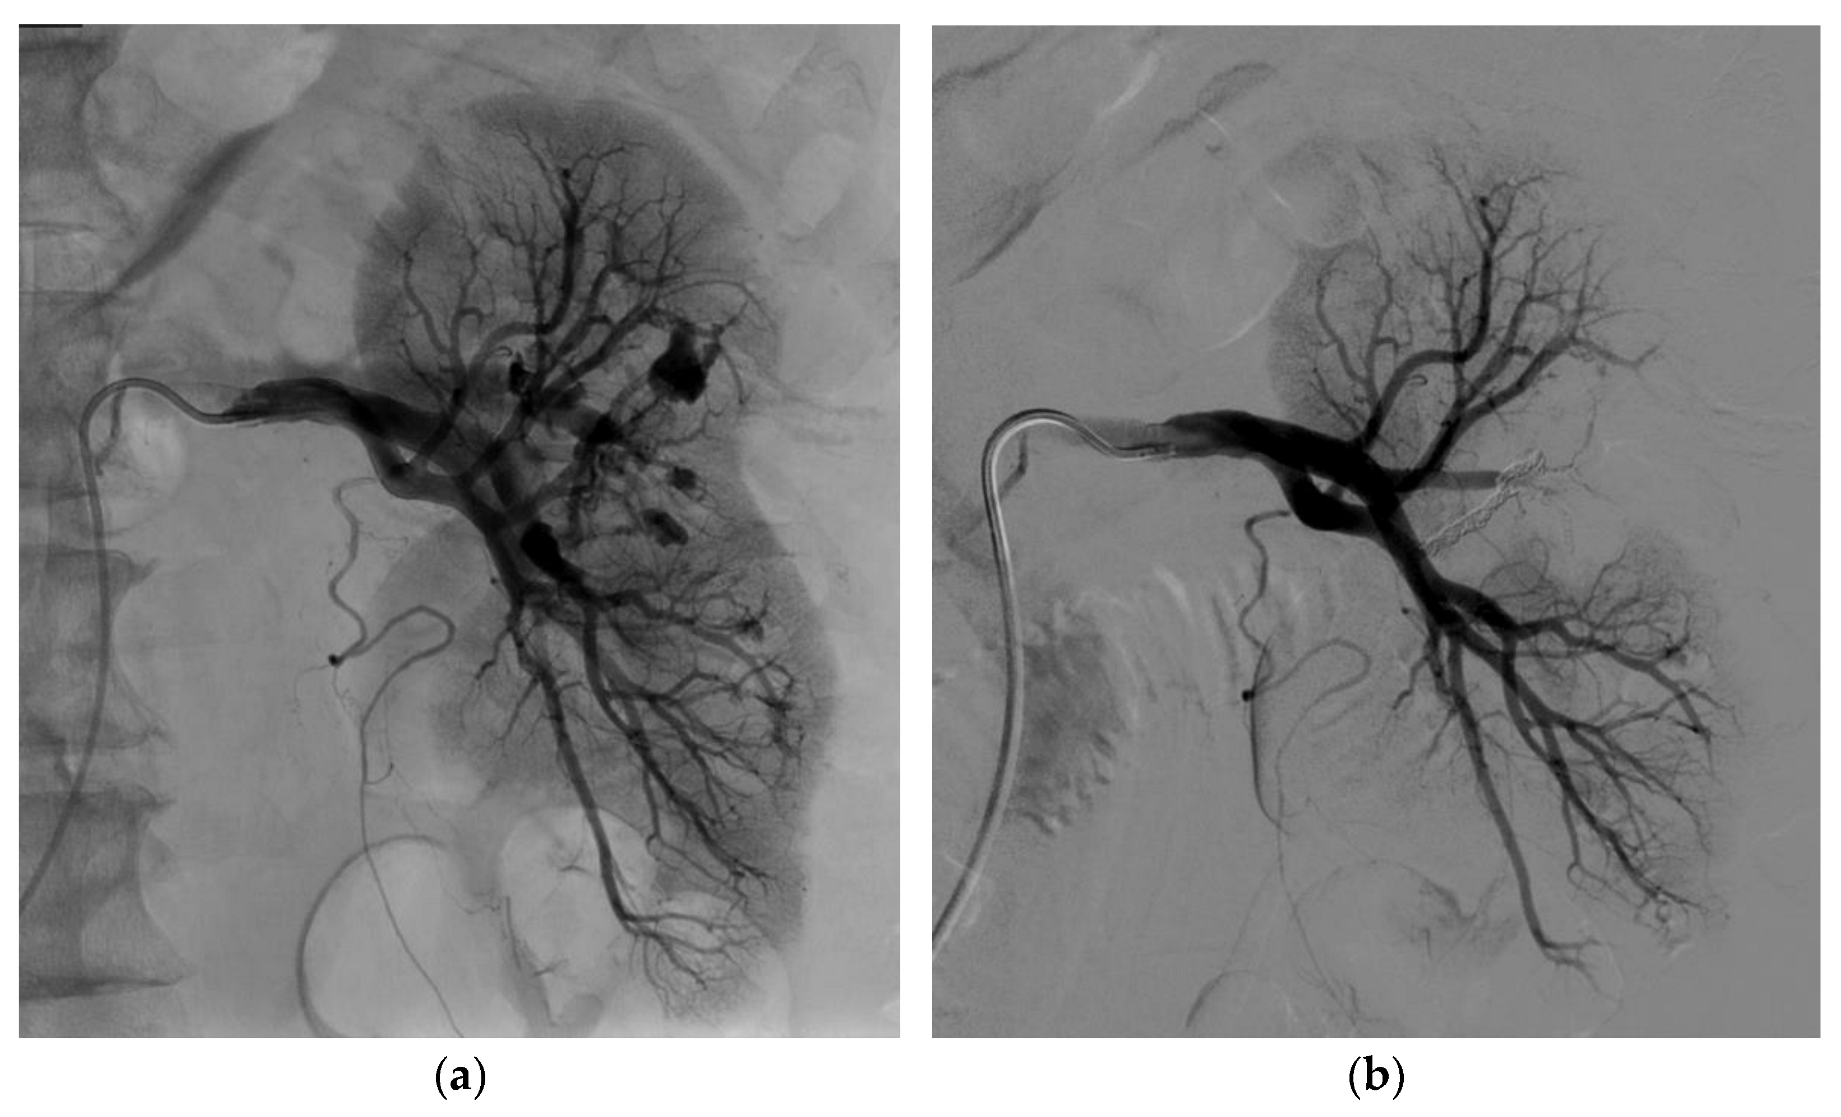

3.2. Endovascular Treatment

| Embolization technique | |

| Coils | 8 (32%) |

| Liquid embolic agent | 8 (6 Glubran2, 1 Onyx, 1 Gelatispon) (32%) |

| Coils and liquid embolic agent | 9 (36%) |

| Technical success at first attempt | 24 (96%) |

| Technical success at first or second attempt | 25 (100%) |

| Clinical success, one attempt | 24 (96%) |

| Clinical success, one or two attempts | 25 (100%) |